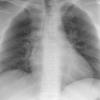

Normal PA

24 yo male

Date: 06/08/2016

Views: 6302